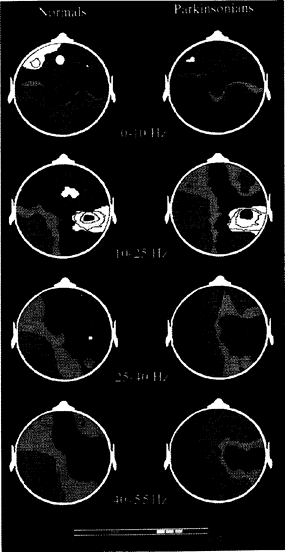

Analisi Statistica delle Mappe Topografiche dei Potenziali Evocati Somatosensoriali a Breve Latenza in Soggetti Normali e Parkinsoniani

- Integrare l’analisi temporale (picco N30) con la mappatura topografica nello spettro di potenza dei potenziali evocati somatosensoriali a breve latenza (SEP) registrati in soggetti parkinsoniani e in soggetti di controllo normali.

- Analizzare con un nuovo approccio statistico le differenze topografiche tra i due gruppi nei domini del tempo e della frequenza

L’obiettivo principale era identificare con maggiore precisione la topografia delle aree frontali del cuoio capelluto dove l’ampiezza dell’onda N30 risultava significativamente ridotta nei soggetti parkinsoniani.

La procedura statistica si è basata sull’uso combinato dell’analisi descrittiva dei dati (DDA) e dell’analisi multivariata, utilizzando una versione migliorata della Significance Probability Mapping (SPM) per valutare dati omo e NON omoschedastici con test parametrici.

Le differenze tra i gruppi sono state valutate con il Test Multivariato Hotelling’s T² e il relativo Test Post Hoc. Questo approccio ha permesso di determinare che le differenze statisticamente significative tra i gruppi, sia nel dominio temporale che in quello dello spettro di potenza, erano localizzate unicamente nelle aree frontali mediali e controlaterali del cuoio capelluto.